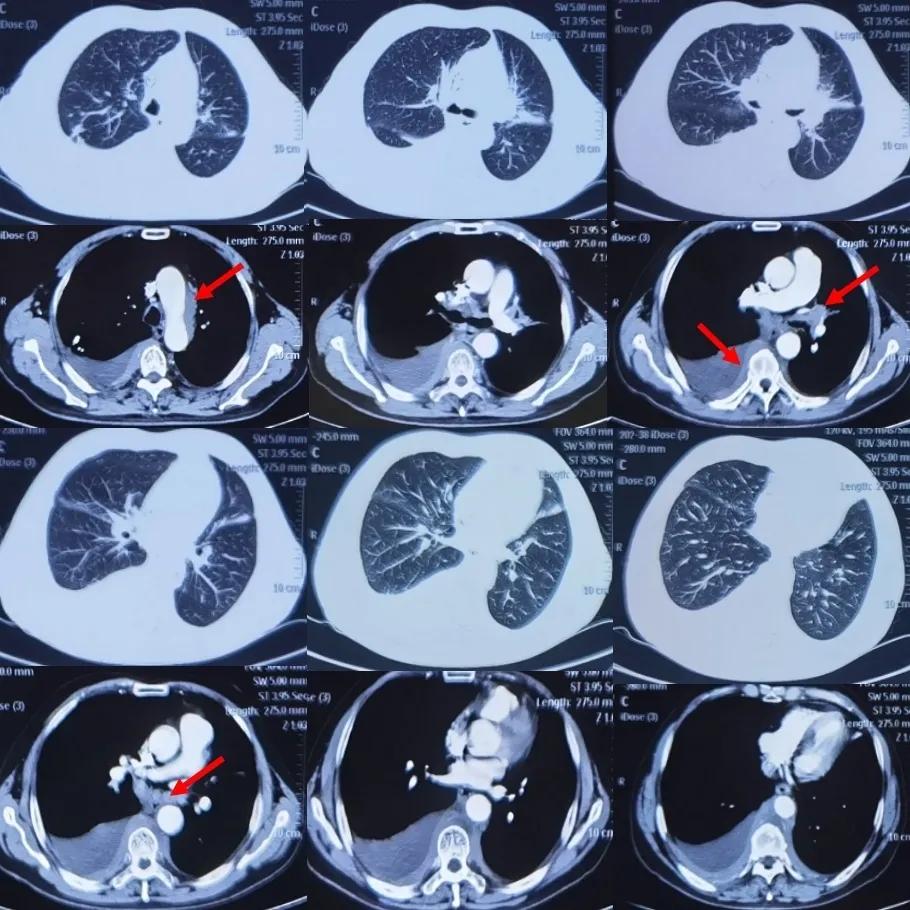

胸部增强CT(2020年9月4日在南昌市某三甲医院)(图3):

图3:南昌市三甲医院胸部CT增强(2020年9月4日)

CT报告,患者原发性支气管肺癌伴纵隔,两肺门,横隔组,肝胃间隙多发淋巴结转移,双侧胸膜转移,包绕血管并右侧胸腔及叶间积液。胸部增强CT(2020年9月10日 上海市某三甲医院):左肺上叶支气管狭窄,伴周围软组织影,纵隔内肿大淋巴结伴融合,两肺胸膜增厚,两侧胸腔积液,恶性待排。主动脉弓旁条状低密度影。右肺上叶钙化灶,右肺中叶斑片状磨玻璃影。胸部CT增强(2021年5月28日 上海市某三甲医院)(图4):

图4:胸部CT平扫对比:①2020年11月9日南昌市某三甲医院(抗感染治疗后复查);②2021年2月17日南昌市某三甲医院(症状加重后复查,抗结核治疗前);③2021年5月21日上海市某三甲医院(抗结核治疗后复查)

从CT影像学我们可以看到,患者左肺上叶支气管狭窄,伴周围软组织影,纵隔肿大淋巴结伴融合,两侧胸膜增厚,右侧液气胸引流中,左侧胸腔积液;较2021年5月21日右侧胸腔积液减少、积气新发。主动脉弓旁条状低密度影,建议结合临床病史。右肺上叶钙化灶,右肺中叶斑片磨玻璃影。后纵隔软组织影:至此,引出一个思考,是纵隔纤维化吗?